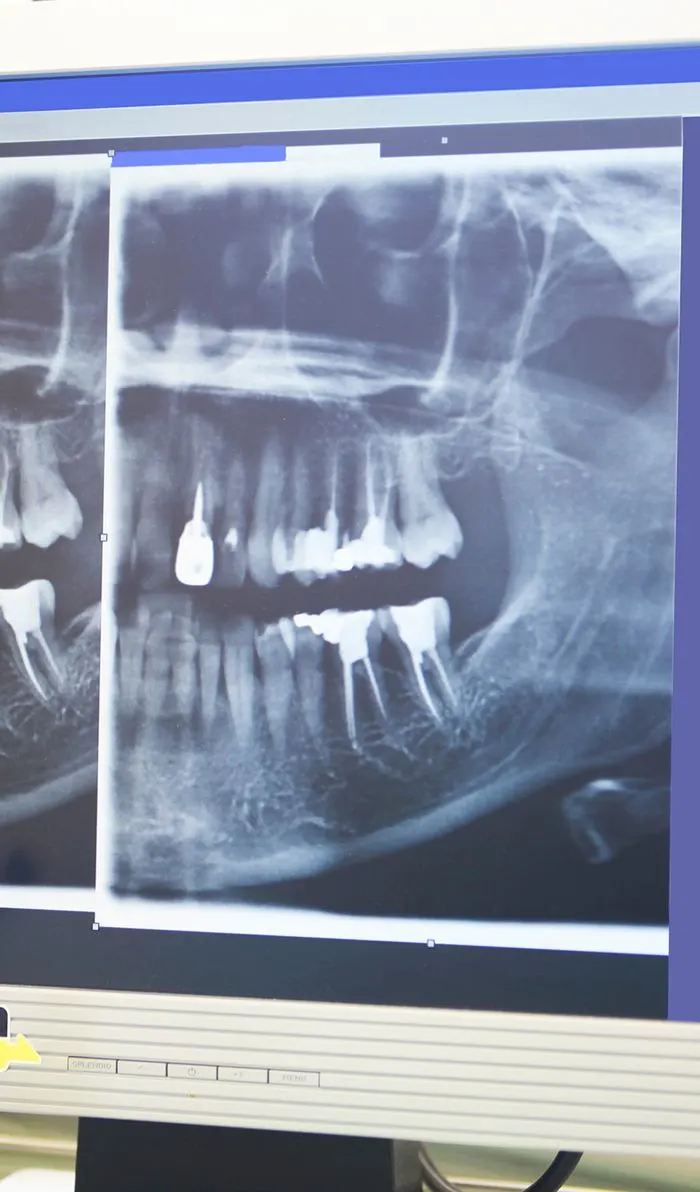

X-ray

Your dentist will begin with a comprehensive examination of your tooth and x-rays to identify the cause of your dental discomfort. If an infection is present, they'll assess its severity to determine if a root canal is the appropriate treatment option.If root canal therapy is necessary, your dentist will ensure the treatment area is completely numb, including the nerves. Before starting the procedure, they'll discuss various sedation options with you to ensure your comfort throughout the treatment.